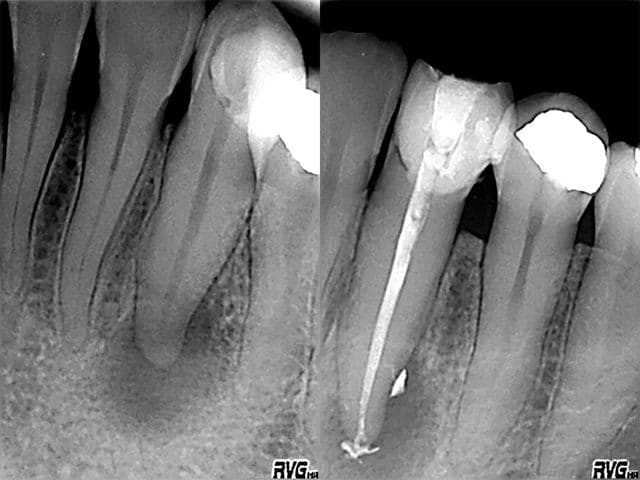

Images eb1m5g - Eugenol